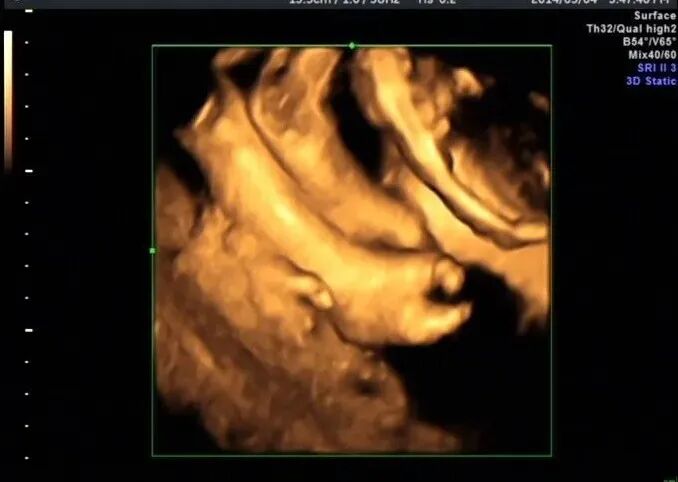

再看脚也不对劲,马上启动三维超声,下图是三维超声表现

手脚都有问题,呈龙虾爪样,非常典型的手裂足裂,胎儿父母没有啥疾病

最后孕妇选择了引产,下图是引产照片

引产结果跟超声图像一样,父母都做了基因检查结果正常。